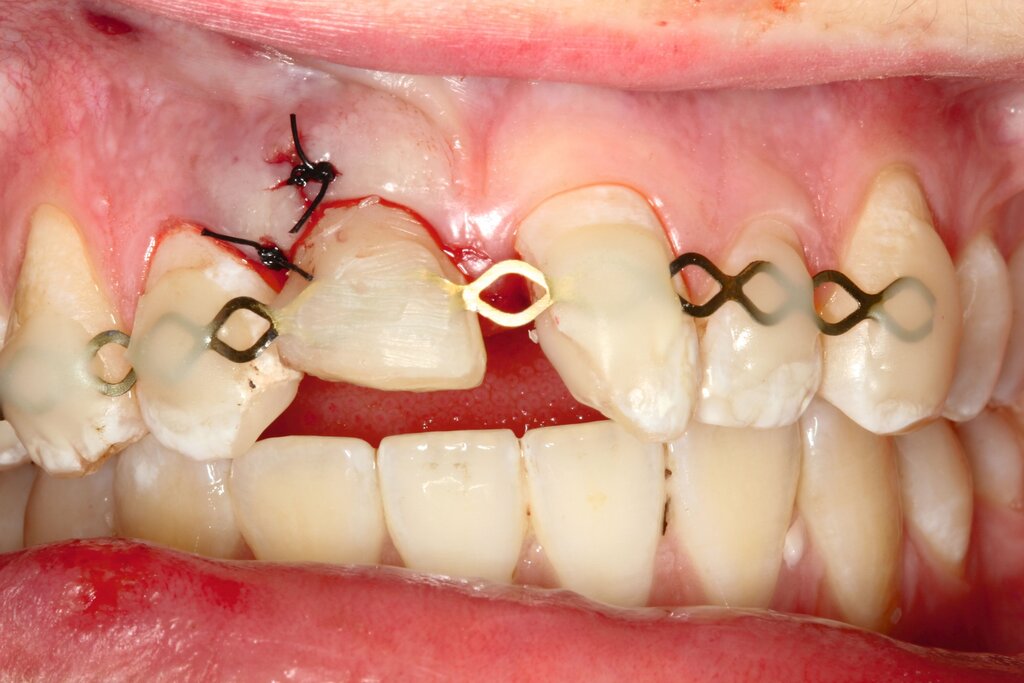

Alternativ dazu bietet sich die Koronalverlagerung der Defektgrenze mit gleichzeitiger Wiederherstellung der biologischen Breite durch eine kieferorthopädische (siehe Teil 5 der Fortbildung „Dentales Trauma“: Kieferorthopädische Aspekte) oder die chirurgische Extrusion an (Abbildung 2).